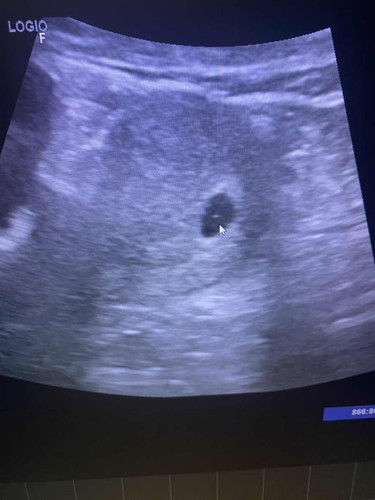

8 w เจอแต่ถุงการตั้งครรภ์ กังวลมากเลยค่ะกลัวท้องลม

9wยังไม่เจอตัวอ่อนเหมือนกันคะเจอแต่ถุงการตั้งครรภ์กังวลเหมือนกันกลัวจะเป็นท้องลม